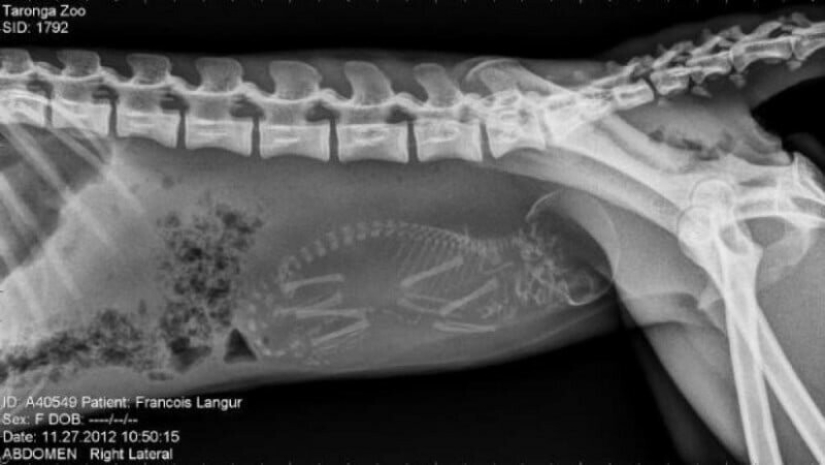

Pregnant monkey